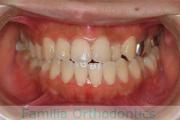

No.20V-557

- 主な症状:

- 上顎前突

- その他の症状:

- 叢生

- 24歳

- 女性

- 抜歯部位

- 上:

- 44

- 下:

- 55

- FEA

- 90万円

前歯を下げて口元をひっこめたいということで来院されました。かなり強い上顎前突(出っ歯)で、アンカースクリューとマルチブラケット法を用いて上下左右から小臼歯を抜歯して治療を行いました。3年半、40回程度の通院をしていただきました。

かみ合わせが深いため、前歯の圧下(歯ぐきに押し戻す動き)が必要なため、歯根吸収のリスクが高いケースでした。